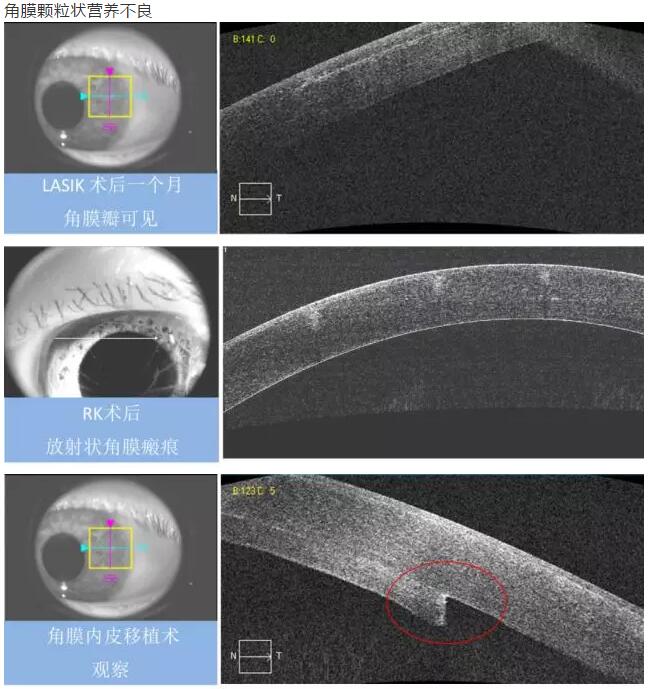

2、角膜厚度评估,角膜水肿、瘢痕、混浊、溃疡、异物、炎症、胬肉等断层观察

3、角膜屈光手术后角膜瓣观察、角膜厚度评估等

4、后弹力层角膜内皮移植术(DSEK)、板层角膜移植术、白内障术后内皮层脱落等术后观察